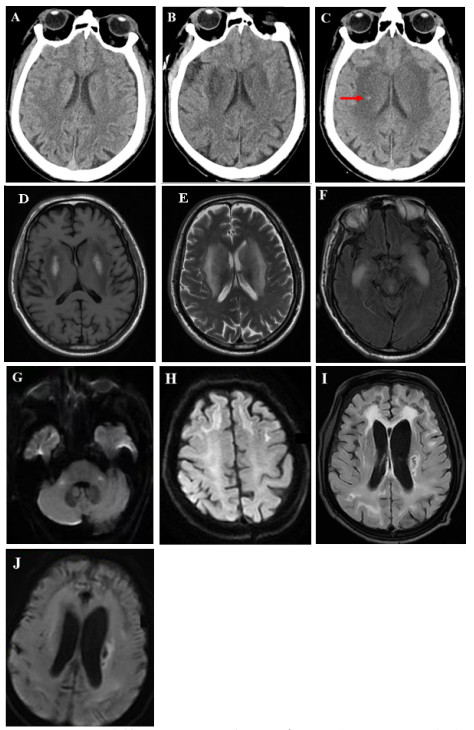

| 注:(A)入院第1天CT示双侧脑室旁见对称性月晕状稍低密度影;(B)入院第5天CT示双侧基底节区对称性低密度灶,较前显著;(C)入院第15天CT示双侧基底节区病灶较前密度减低,新增小片状高密底影,提示小出血灶(箭头所示);(D-H)入院第9天MRI示双侧基底节区呈对称性长T1长T2信号,伴有脑肿胀;FLAIR序列双侧颞叶深部对称性高信号影;DWI序列双侧桥臂、额叶皮层下白质多发斑点片状及条片状高信号影;(I-J)出院第6个月MRI示FLAIR和DWI序列双侧基底节区仍见多发斑点状及条片状异常信号影,较前高信号减低,范围缩小,脑室系统明显扩大,皮层萎缩 图 1 本例患者头颅影像学动态演变 |

患者入院后即行血液灌流(3次/d,共2 d)清除毒物、连续性肾脏替代治疗纠正内环境紊乱、血管活性药物维持血压、补液促进毒物排泄及对症支持等治疗。中毒后第5天,患者仍深昏迷,GCS评分2T(E1VTM1)。复查头颅CT:双侧基底节区对称性低密度灶,较前片明显,见图 1B。中毒后第9天,意识状况仍无改善,检查头颅MRI:双侧额顶颞枕叶皮层下、基底节区、桥臂多发异常信号,伴脑肿胀,考虑中毒性脑病,见图 1D~图 1H;磁共振动脉自旋标记(arterial spin labeling, ASL):两侧额颞叶皮层下白质区对称性灌注增高,两侧基底节、小脑、枕顶叶对称性灌注减低,符合中毒性脑病改变,见图 2A~图 2C。针对意识障碍治疗予纳洛酮静脉滴注;针对脑水肿予20%甘露醇静脉滴注(每次150ml,第1周每8小时1次,第2周每12小时1次),甲泼尼龙静脉注射(每次40mg,第1周每日2次,第2周每日1次)。中毒后第7天行床旁气管切开,中毒后第15天呼吸循环稳定,停用呼吸机,但仍处于昏迷状态,无气道自洁能力,GCS评分5分(E2V1M2)。中毒后第15天复查头颅CT:双侧基底节区病灶较前密度减低,新增小片状高密度影,提示小出血灶,见图 1C。

患者中毒后第20天出院,并转至本地康复医院继续治疗,方案包括高压氧促进脑功能恢复、药物预防癫痫发作,辅以低频电刺激、电动起立床训练、针灸等康复治疗。康复过程中患者持续经鼻饲进食,大小便无法自控,中毒后第3个月GCS评分7分(E2V2M3)。坚持以上康复方案,中毒后第6个月,GCS评分10分(E3V3M4)。复查头颅MRI:双侧额顶枕叶皮层下可见少许斑点片状及条片状DWI稍高信号影,较前高信号减低,范围缩小,脑室系统明显扩大,皮层萎缩,见图 1I ~图 1J。磁共振ASL:双侧额顶枕叶、小脑半球灌注弥漫性减低,损害范围较前扩大,见图 2D~图 2F。动态随访,中毒后第10个月,患者意识状况稍改善,能自主睁眼,简单应答,对刺痛能明确定位,能经口进食,GCS评分12分(E4V3M5)。随访至中毒后第15个月,患者神经功能较前不再有显著变化。